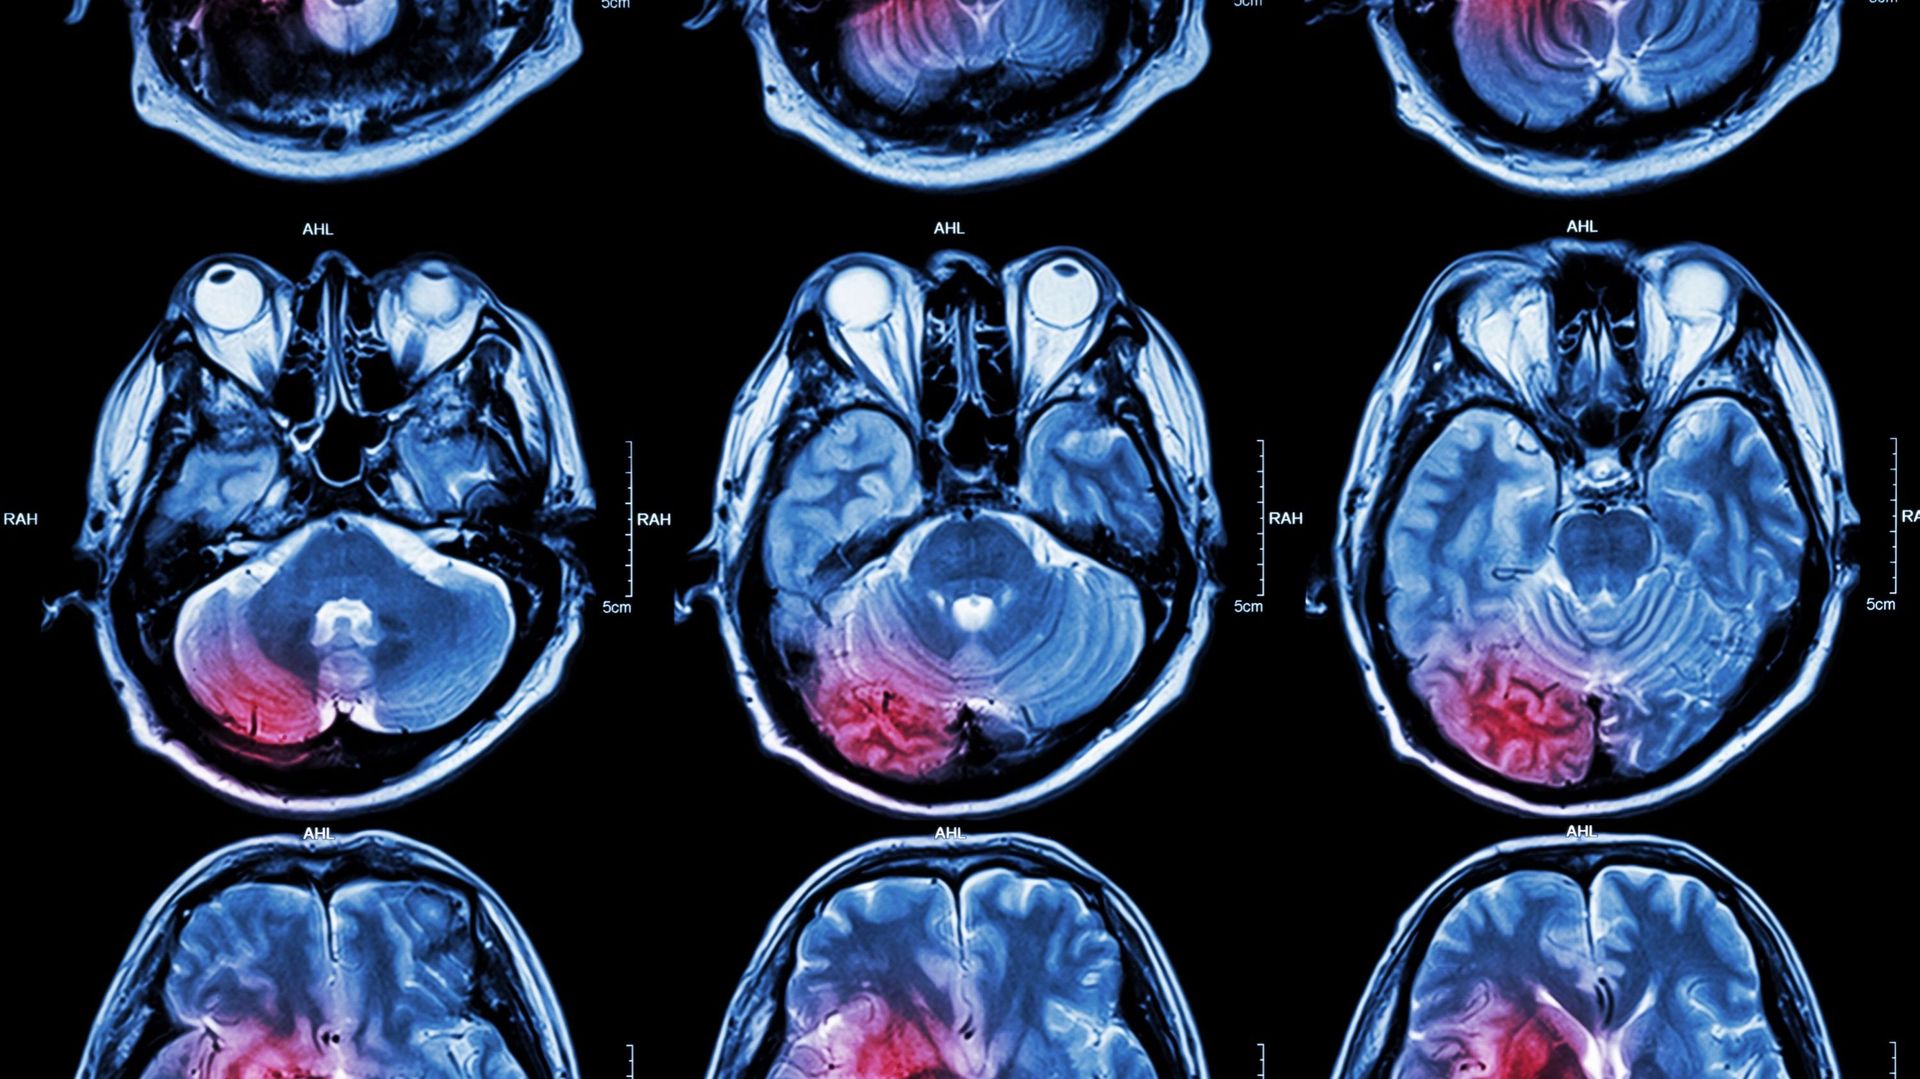

Le nombre de victimes d'AVC recensé a augmenté de 50% en 25 ans